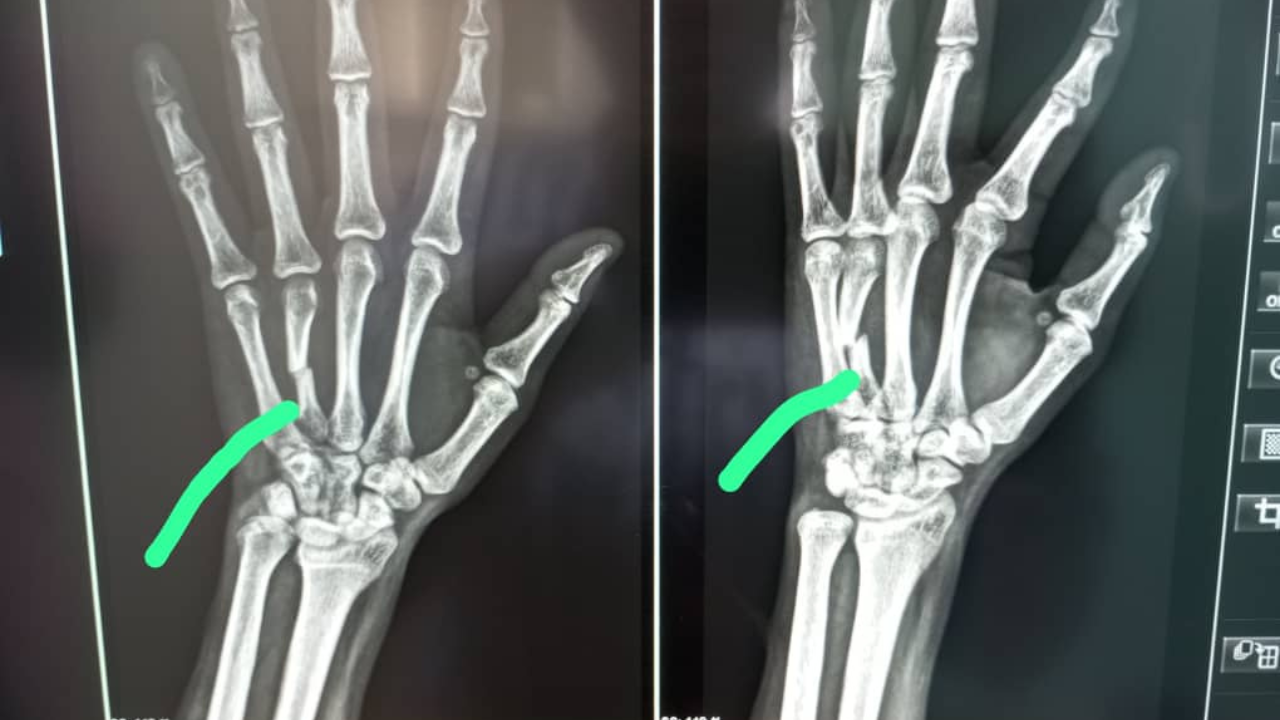

De linkse van Trust Ncube

oktober 24, 2025

In september 2025 ontving Simon een hulpvraag over Trust Ncube.Trust, een 31-jarige man, had een auto-ongeluk gehad waarbij zijn linkerhand was gebroken. Op de foto was een duidelijke breuk te zien, die met een metalen ...